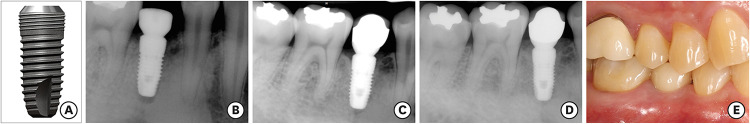

Purpose: This study retrospectively investigated the long-term clinical and radiographic outcomes of a bone-level type, 2-piece, internal connection dental implant system characterized by coronal microthreads.

Methods: A total of 872 implants placed in 284 patients were selected from 1,845 implants placed in 691 patients by experienced periodontists at Yonsei University Dental Hospital. These selected implants had been followed up for over 10 years and were included in the present study. A statistical evaluation of implant survival and treatment success, based on changes in marginal bone levels, was conducted using electronic records and consecutively taken radiographs.

Results: Over a follow-up period of 12.3±2.0 years, 830 of the 872 implants remained intact, yielding a cumulative survival rate of 95.2% at the implant level and 88.4% at the patient level. The cumulative treatment success rates, characterized by marginal bone loss of less than 2 mm, stood at 87.0% for implants and 76.1% for patients. Among the 830 surviving implants, 113 fixtures were classified as ailing, with an average marginal bone loss of 4.09±1.44 mm. Cox regression analysis revealed that implants 8 mm in length or shorter were significantly more likely to fail or experience pathologic marginal bone resorption, with hazard ratios of 3.71 and 2.00, respectively (P<0.05).

Conclusions: The survival and treatment success of the investigated microthreaded, bone-level, 2-piece, internal connection implants were acceptable over a follow-up period exceeding 10 years. However, shorter dental implants exhibited a higher propensity for failure and excessive marginal bone loss.